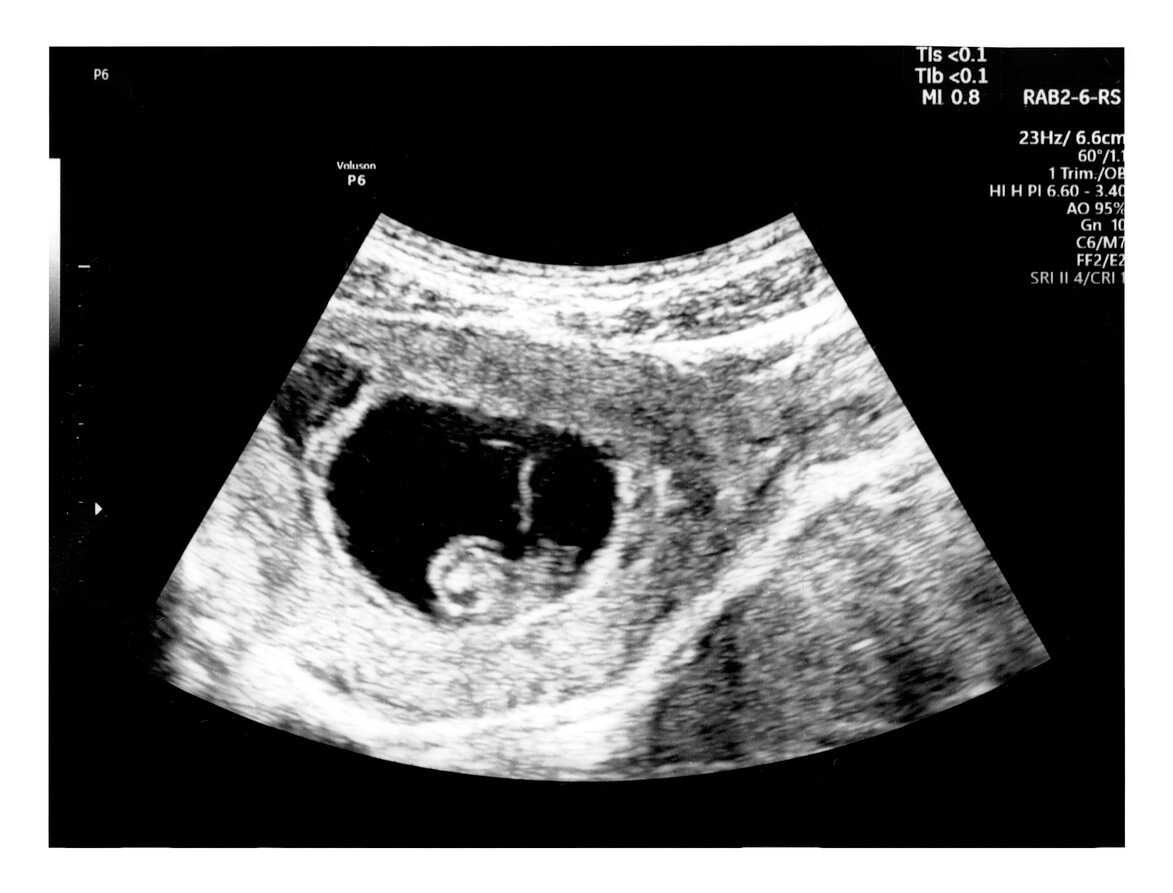

En la ecografía de las 6 semanas se observa gran parte de estos cambios, evidenciado por las siguientes estructuras:

- Un círculo ovalado negro, que es el saco gestacional. Esta esfera pequeña y oscura mide unos 8 milímetros para este momento. Dentro de esta estructura se encuentran la cavidad amniótica, el saco vitelino y el futuro bebé.

- Un anillo blanco dentro del óvalo negro, que es el saco vitelino, donde se alimenta el bebé en las primeras semanas de gestación.

- En ocasiones puede observarse el embrión (conocido también como polo fetal) y escucharse el latido del corazón del bebé.